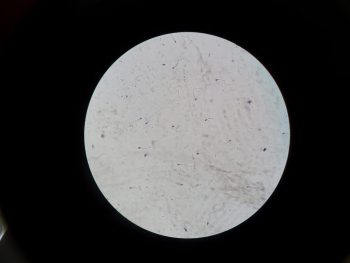

Tinh trùng Y là gì? Bí quyết bồi bổ tinh binh để sớm đón quý tử

Chào Anh Em! Dạo gần đây, Lão nhận được rất nhiều câu hỏi từ các cặp vợ chồng đang mong...